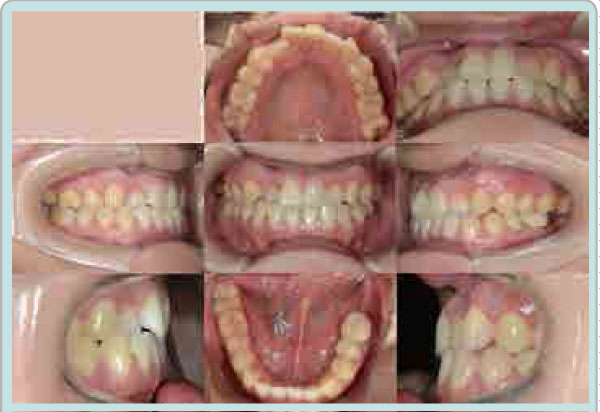

A 34-year-old female patient came with a chief complaint of “unattractive smile due to the crowded dentition and anterior crossbite”. The extra-oral examination showed mild concave profile. The nasolzbizl angle was slightly obtuse (100°). The intraoral findings revealed upper anterior teeth crowding, dental crossbite and a maxillary canine missing.

The space analysis showed 8.0 mm of space deficiency in the upper dentition and 1.5 mm space deficiency in the lower dentition. Both upper and lower dental arches were symmetric ovoid shape (Figure 1). Panoramic findings showed #13 missing and #27 elongation (Figure 2). Cephalometric analysis indicated that this patient had a skeletal Class I pattern with an ANB angle of 3.4 ° with a mean mandibular angle. The upper incisor positions showed tendency of mild retroclination measured from U-1 to A-P plane of 5.3mm. The mandibular incisors were retroclined as compared to norms. (Figure 3, Table 1).

Figure 1: Before orthodontic treatment. Extra-oral photos and intra-oral photos.